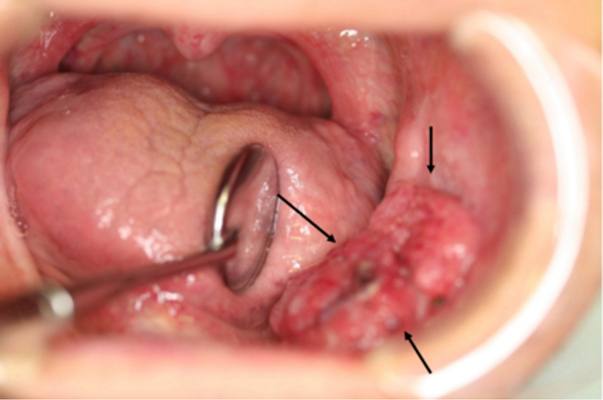

A:舌癌一般是在舌側緣出現腫物,有外生型、潰瘍型和浸潤型。最常見的是外生型和潰瘍型,一般在早期就是在舌側緣出現一個深的潰瘍,而且潰瘍長期不愈。和普通的口腔潰瘍不同,舌癌的潰瘍兩個月以上也不會自行癒合,創面不斷的增大、加深,加深到一定程度舌頭會出……

A:吃辣的舌頭疼應該不是舌癌,辣不是種味道而是種燒灼感,所以吃辣的出現舌頭疼是正常現象,也就是辣椒素刺激了舌黏膜引起疼痛感。舌癌不是這樣的表現,舌癌發生在舌側緣,有外生型也有潰瘍型。外生型的是向表面突出,表面黏膜不是光滑、完整的,有的是呈菜花樣……

A:舌癌是口腔頜面部常見的一種惡性腫瘤,多數為鱗狀細胞癌,多見於舌緣,常為潰瘍型或浸潤型,增長快,疼痛明顯,浸潤性強,可導致舌運動受限,進食及吞嚥困難,男性多於女性。舌癌的病因目前尚不明確,多數認為與環境因素有關,另外,神經因素,內分泌因素,機……